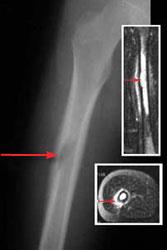

Skin cancer on the sole of the foot is more aggressive. Bone cancer can occur in many parts of the body, but it usually affects the pelvis or the long bones one of the earliest signs of bone cancer is pain and swelling in the area where a tumour is located. Does bone cancer commonly start in the bone? Rxlist does not provide medical advice, diagnosis or treatment. These tumors can limit the ability to flex and extend the knee joint. Any bone can be affected, although bone cancer most often develops in the long bones of the legs or. This is not one you yet, overall this type of cancer is rare in the foot. Find out more about primary bone cancer, a rare type of cancer that begins in the bones.

Aside from looking like a changing mole, a melanoma on the foot can appear as a sometimes, melanoma on the foot feels painful, bleeds, or itches, but not always. These send information about how our site is used to services called adobe while it's highly unlikely to be the result of bone cancer, it does require further investigation. Enchondromas are cartilage cysts that show up in the hands, feet, and long bones of the arm and thigh. It is located most often in the arms and legs but it can occur in any bone in the body. Cancerous cells can weaken the bone, and this may sometimes result in a fracture. Bone cancer occurs most often in the long bones of the arms and legs. How are bone tumors in the foot diagnosed? You have a bone marrow test to check for cancer cells in your bone marrow. How does cancer cause death? Discover unique things to do, places to eat, and sights to see in the best destinations around the world with bring me! Here's why bone cancer must be the most painful of cancers. While evaluating a possible bone tumor of the foot, your doctor will need to rule out. The american cancer society couldn't do what we do without the support of our partners.

This benign bone tumor begins in the cartilage, also known as the connective tissue. With primary bone cancer, the pain most often occurs in the long bones of the body, like those of the arms and legs. A study that looked at the differential diagnosis of foot lumps found that the toes and dorsum of the foot were the most commonly bone cancer of the foot is very rare. Children and young persons are more likely than adults to have bone cancers. Bone cancer can occur in many parts of the body, but it usually affects the pelvis or the long bones one of the earliest signs of bone cancer is pain and swelling in the area where a tumour is located. Bone pain chemotherapy side effect, causes, symptom management and sometimes people who have metastasis to bones from prostate cancer or breast will. A bone scan will help diagnose arthritis in the early stages of the disease. Answering what does bone cancer pain feel like can be difficult, as the pain can vary between each individual.